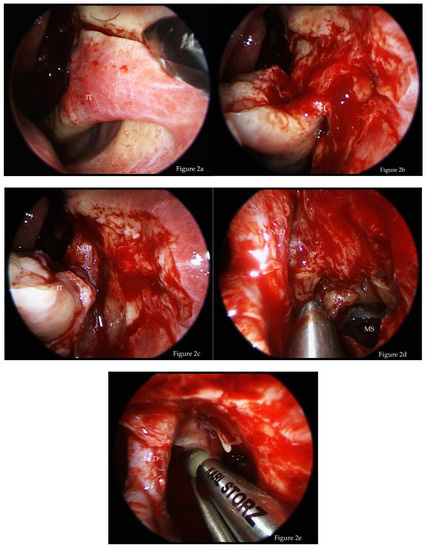

Surgical Technique

- debulking of the exophytic tumor inside the nasal cavity;

- uncinectomy, middle meatal antrostomy type III, with or without opening of the bulla ethmoidalis and an anterior ethmoidectomy;

- entry of the maxillary sinus via the prelacrimal approach with complete exposure of the IP and its attachment;

- creation of a medially based mucosal flap from the nasal floor towards the maxillary sinus;

- subperiosteal resection of the IP and drilling of the bone at the attachment site until the bone shows a clear white color and healthy appearance. In some cases, some parts of the maxillary wall need to be completely resected to the level of the periosteum of the hard palate and the pterygopalatine fossa;

- resection of the nasolacrimal duct if necessary due to tumor invasion;

- performing a medial maxillectomy; and,

- repositioning the mucosal flap and the inferior turbinate, which is sutured to the mucosa of the lateral nasal wall with one or two stitches.